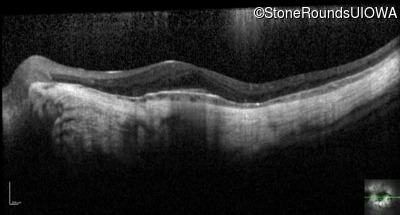

Optical Coherence Tomography - Right - 20/40 -2

Exemplar / OCT Stack